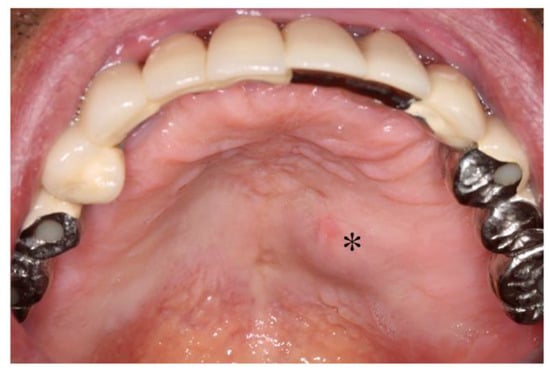

2.2. Dental Examination